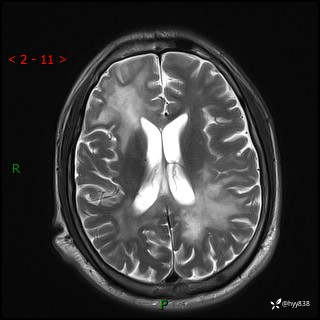

辅助检查:MRI

MRI T2WI